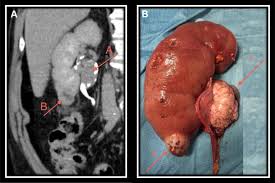

Management Of Patients With Upper Urinary Tract Transitional Cell Carcinoma Nature Reviews Urology from media.springernature.com In time, signs and symptoms may develop, including: The abdomen may feel very full or heavy, and the person may also have lower back pain. The rate of new kidney and renal pelvis cancer diagnoses increased only slightly over time with about a 1% increase in cases each year between 2003 and 2016. The renal pelvis is the top part of the ureter. As a rule it is painless. Other health conditions can cause the same symptoms as cancer of the renal pelvis or ureter. Blood in the urine (pee), which is called hematuria The most common symptoms of ureter and renal pelvis cancer are blood in the urine (pee), called haematuria, and pain in one side of the lower back.

Cancer is when cells in the body grow out of control, often forming a mass or tumor. In upper urinary tract cancer, abnormal cells are found in the renal pelvis, renal calyces and/or ureters. The renal pelvis is the top part of the ureter. There were 1,099 cases of kidney and renal pelvis cancer diagnosed and 241 deaths from kidney and renal pelvis cancer in 2016. Signs and symptoms of transitional cell cancer of the renal pelvis and ureter include blood in the urine and back pain. The risk of ureteral cancer increases with age. It could also occur in the ureter, or in the urethra. The most common symptoms of ureter and renal pelvis cancer are blood in the urine (pee), called haematuria, and pain in one side of the lower back. The same symptoms can also come from other causes. In time, signs and symptoms may develop, including: Renal pelvic and ureteral cancers. The rate of newly diagnosed kidney cancers is increasing. If the tumor is located beyond the ureter and renal pelvis, the cancer may quickly metastasize to the kidney or other organs, reducing chances for survival.

Kidney Cancer Causes Symptoms And Diagnosis from www.shalby.org The pathogens reach the renal pelvis via the urethra, bladder and ureter.therefore, inflammation of the renal pelvis is often preceded by urethritis or cystitis. Certain factors affect prognosis (chance of recovery) and treatment options. Renal pelvic and ureteral cancers. Tests that examine the abdomen and kidneys are used to detect (find) and diagnose transitional cell cancer of the renal pelvis and ureter. The ureter is a long tube that connects the kidney to the bladder. Management of metastatic renal cell. Symptoms of renal pelvis and ureter cancer blood in the urine is usually the first symptom. The abdomen may feel very full or heavy, and the person may also have lower back pain.